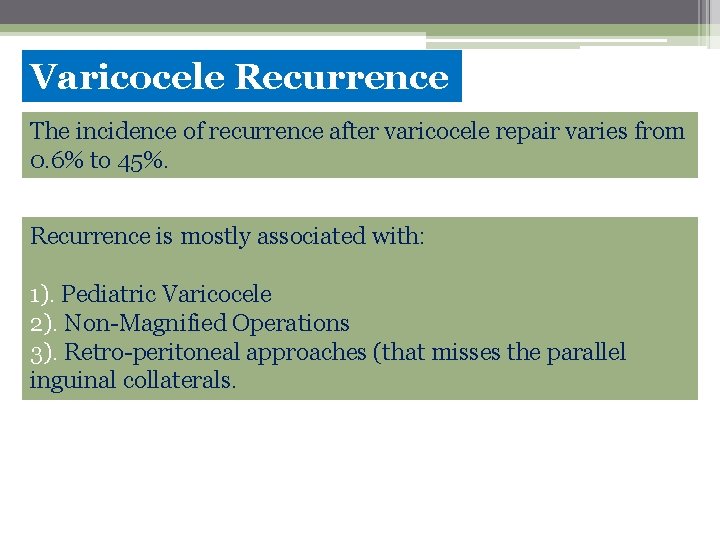

Varicocele Recurrence The incidence of recurrence after varicocele repair varies from 0. 6% to 45%. Recurrence is mostly associated with: 1). Pediatric Varicocele 2). Non-Magnified Operations 3). Retro-peritoneal approaches (that misses the parallel inguinal collaterals.